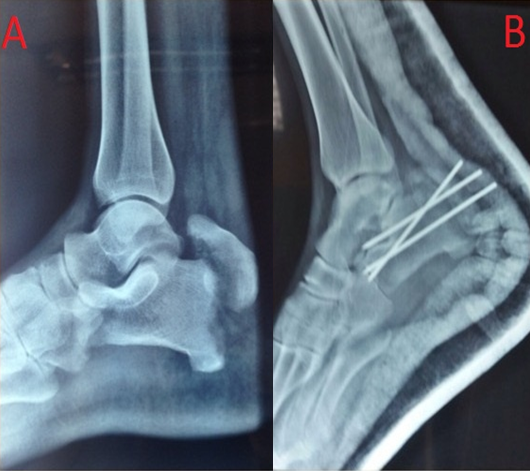

Avulsion calcaneal tuberosity fracture is an uncommon but potentially serious condition. Recent studies on the epidemiology of these specific fractures have demonstrated that avulsed calcaneal fractures account for 1.3% of all calcaneal fractures.It is therefore understandable that little has been written about these fractures. This type of injuries is usually caused by sudden muscular contraction of the Achilles tendon when the heel is flat on the ground. We report a very rare case of avulsion of the tuberosity of the calcaneus. A 47 year old male was admitted to the emergency department withpain and total functional impotence of his right lower limb after falling on the footduring a football game.The X-ray examination showeda displaced extra-articular fracture of the tuberosityof the calcaneus(A).The fixation of this fracture was carried out using an anterior-lateral approach, the large fragment wasstabilized with two kirschner wires (B). After reduction and healing, the patient recovered fully without clinical weakness of the triceps surae.